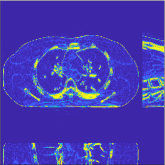

| views | ||||

| (a) , | (b) , | (c) , | (d) , |